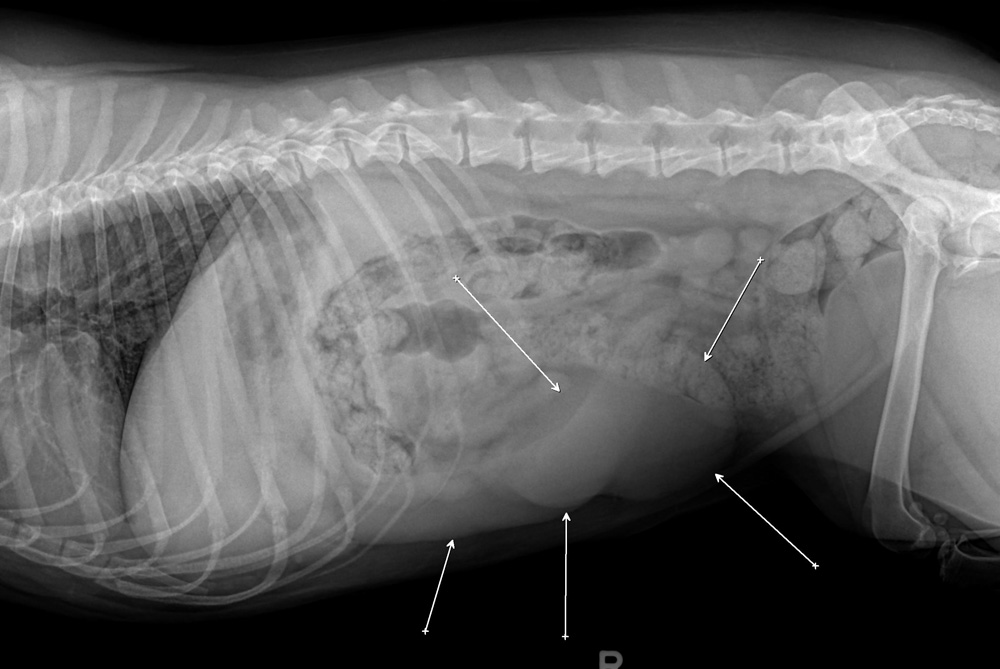

Ваш ветеринарный врач может предположить рак селезенки, основываясь на клинических признаках у животного, и частично на результатах физического осмотра. Часто помогают обнаружить опухоли рентген и УЗИ, но эти неинвазивные процедуры не всегда позволяют отличить гиперплазию от настоящего рака. В пробах крови может обнаружиться анемия, но она неспецифична, и только при некоторых опухолях в крови будут обнаруживаться раковые клетки.

Чтобы точно идентифицировать опухоль, важно получить образец самой опухоли. Для того, чтобы получить образцы тканей для микроскопического исследования, часто применяются диагностические операции. Цитология, микроскопические исследование образцов клеток для опухолей селезенки, как правило, неинформативна. Необходима гистопатология - микроскопическое исследование специально приготовленных и окрашенных срезов тканей. Гистопатология предоставляетт общие и дополнительные сведения, которые помогут определить дальнейшее поведение рака (прогноз).